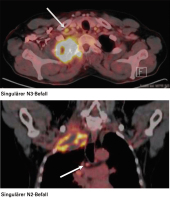

N3-Lymphknoten

Abbildung 5: Diese beiden PET-CT-Bilder verdeutlichen die Wertigkeit eines befallenen lokoregionalen N3-Lymphknotens einerseits und eines subkarinalen Lymphknotens andererseits.

Keywords: LymphknotenPET-CT